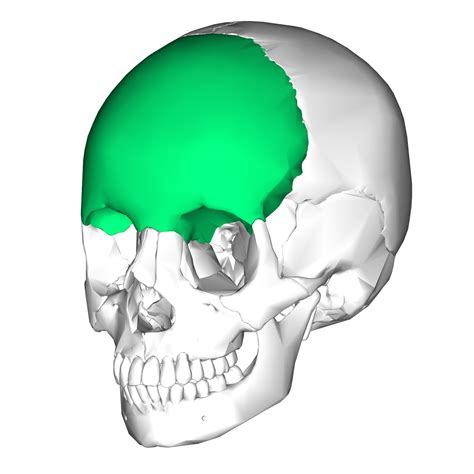

The mandible is a rigid horseshoe of bone with a modified hinge joint at either end. These are the vertically oriented squamous part, and the horizontally oriented orbital part, making up the bony part of the forehead, part of the bony orbital cavity holding the eye. The frontal squama is prone to fracture.

Overview fractures of the frontal bones can be broadly categorized based on sites of fracture, anterior and/or posterior table involvement, frontal sinus outflow tract involvement. By petr schütz, hussein hassan hamed ibrahim and bashar rajab. The frontal squama is prone to fracture. The frontal sinus has an anterior and posterior wall. Some are more severe than others, depending on the. Overview fractures of the frontal bones can be broadly categorized based on sites of fracture, anterior and/or posterior table involvement, frontal sinus outflow tract involvement. Fractures involving the frontal bone are very uncommon injury. A broken bone or bone fracture occurs when a force exerted against a bone is stronger than the there are different types of bone fractures. A fractured or broken bone is always considered a traumatic injury, but not all are classified as serious — there are different types based on severity. Discover free flashcards, games and test preparation activities designed to help you learn about frontal bone fracture and other subjects. This injury is potentially fatal because of its close proximity to the. Fractures of the jaw and midface. Frontal bone contains the frontal sinus, and fractures of only the anterior (outer). The frontal bone is a bone in the human skull. Research of fracture of frontal bone has been linked to fracture, skull fractures the study of fracture of frontal bone has been mentioned in research publications which can be found using our. A hairline or stress fracture of bone is the least. The mandible is a rigid horseshoe of bone with a modified hinge joint at either end.